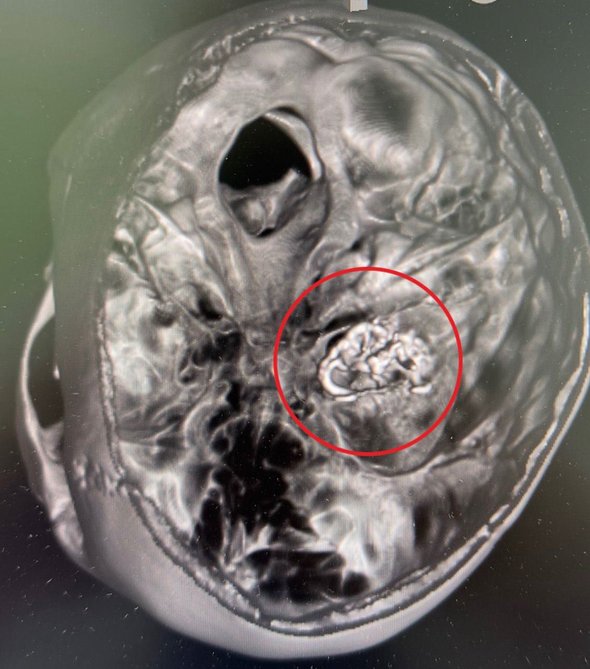

В больницу школьница экстренно поступила в остром состоянии. По словам медиков, проведенное обследование выявило кровоизлияние в мозг из-за лопнувшего сосуда и артериовенозную мальформацию сосудов головного мозга.

При данном виде патологии вены и артерии небольшого диаметра, переплетаясь друг с другом, образуют «сосудистый клубок», в котором произошел разрыв сосуда. Патология опасна тем, что может вызвать повреждение клеток мозга, нарушить их нормальную работу и при несвоевременном лечении привести к летальному исходу.

«Артериовенозная мальформация лечится методом эмболизации — введением в поврежденный сосуд специального вещества для заклеивания места разрыва. Нейрохирурги выполнили процедуру тонким катетером с ювелирной точностью. Операция длилась три часа и позволила „заклеить“ кровоточащий сосуд, снизив риск повторных кровотечений», — рассказал завотделением рентгенэндоваскулярной диагностики и лечения медучреждения Михаил Комиссаров.

фото: vk.com/roshal_kids